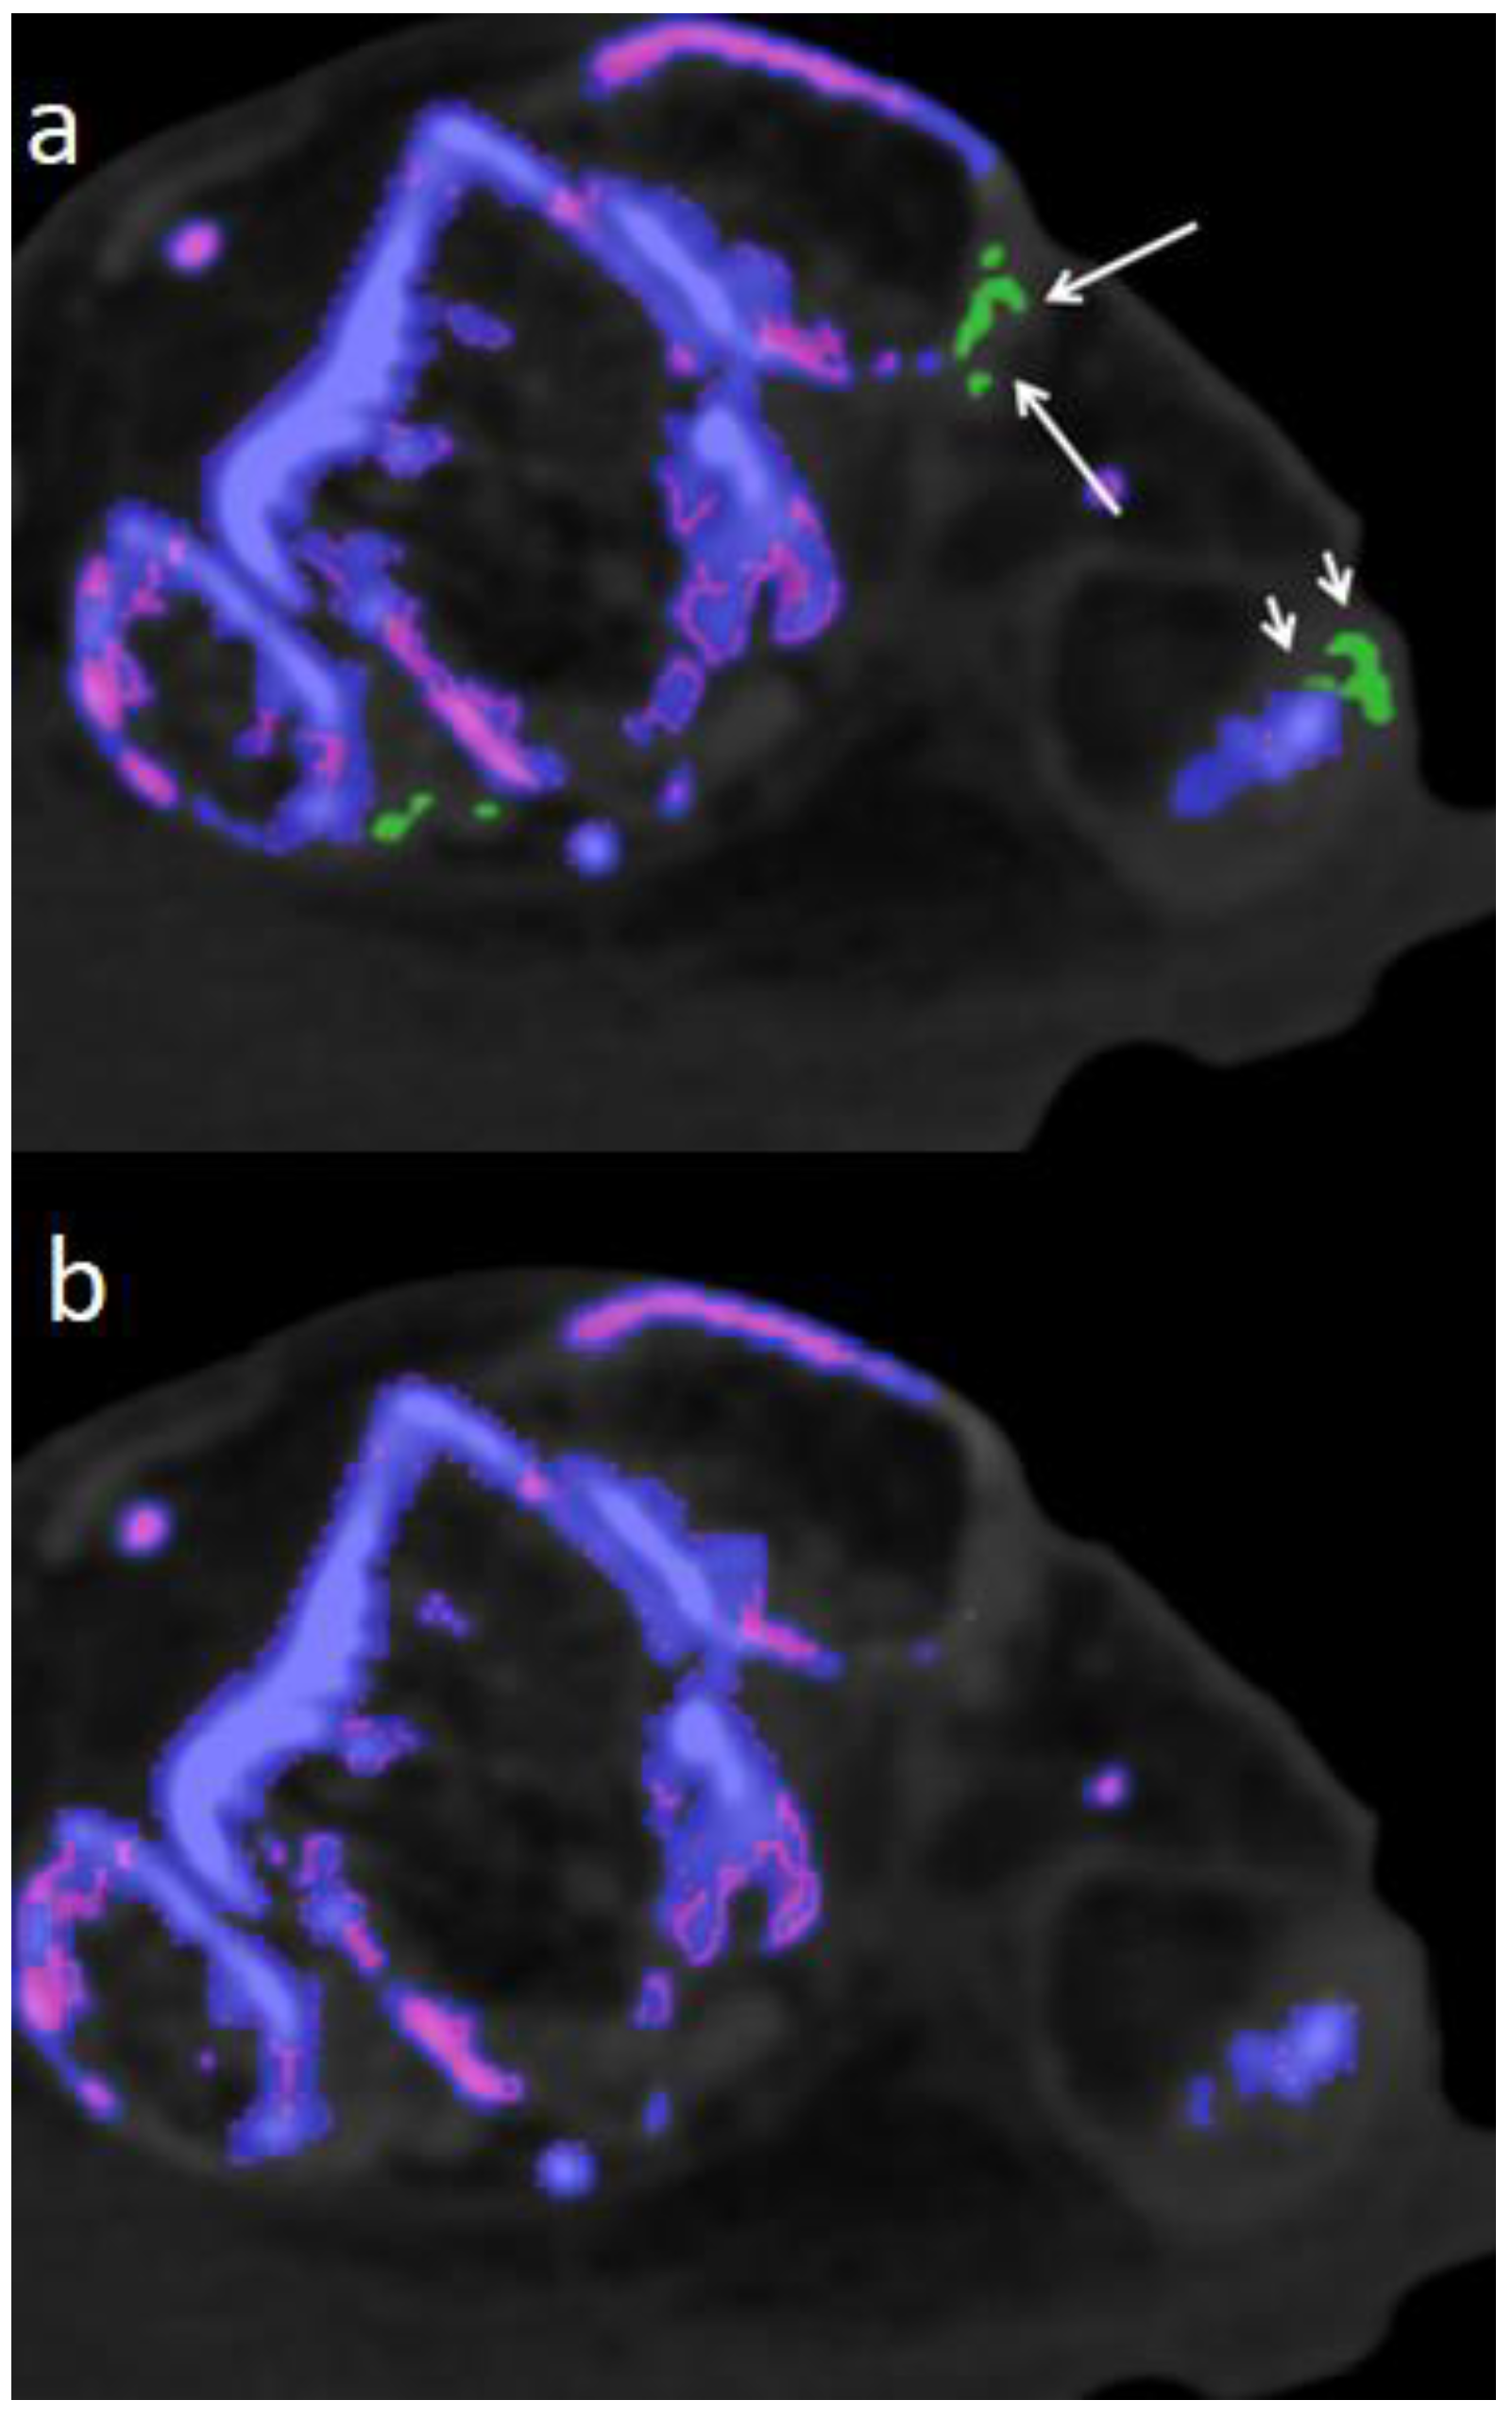

Figure 3. 77 year-old-male fresh cadaver. a.) Polarizing light microscopic evaluation of a sample taken from Achilles tendon, showing large diffuse packed and patchy MSU crystals with strong negative birefringence (bluish structures. b.) Corresponding DECT 120 image showing large MSU deposits in Achilles tendon (large white arrows) and one small MSU deposit (small white arrow) in peroneus tendon. c.) Corresponding DECT 150 image without evidence of MSU deposits in Achilles and peroneus tendon. d.) Polarizing light microscopic evaluation of a sample taken from peroneus tendon, showing diffuse packed and patchy MSU crystals with strong negative birefringence (bluish structures). e.) Corresponding DECT120 image showing MSU deposits in peroneal tendons (white arrows). f.) Corresponding DECT 150 image without any MSU deposits in peroneal tendons.